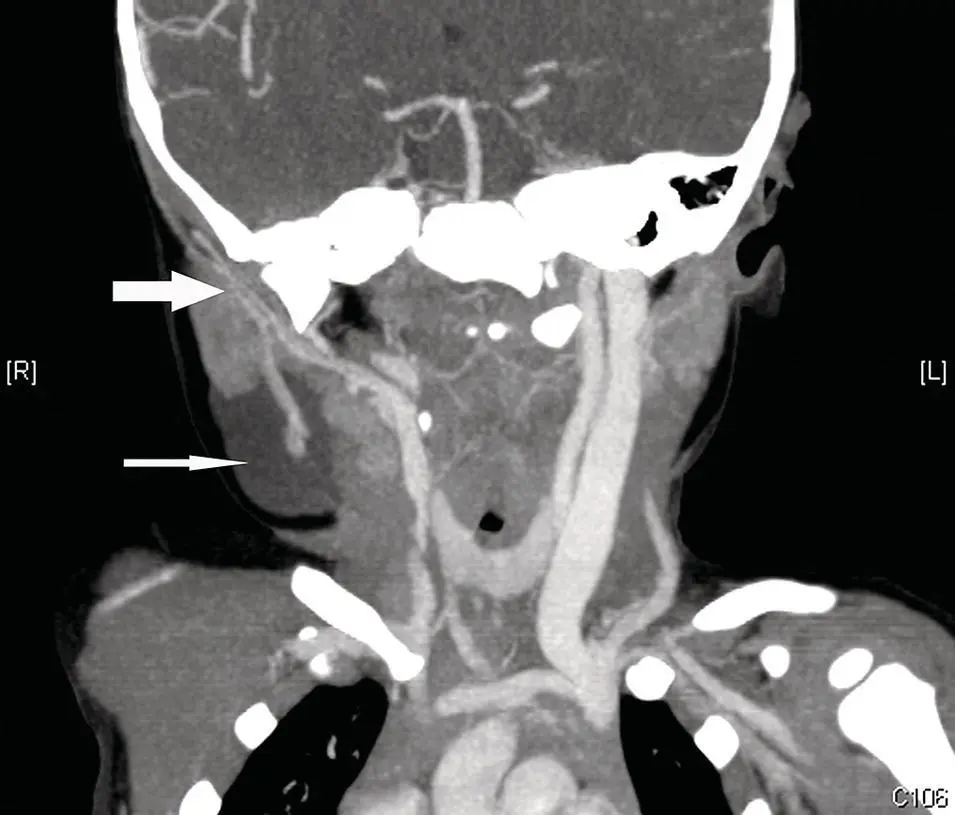

Figure 2.7. CT angiogram (CTA) of the neck at the level of the parotid gland demonstrating the retromandibular vein and adjacent external carotid artery (large white arrow). Note the right cervical lymphangioma (thin white arrow) associated with the tail of the right parotid gland.

CT angiography (CTA) is a powerful method, which allows visualization of arterial vasculature, demonstrating the vascular anatomy of arteries and veins. CTA can be critical in preoperative evaluation to determine the degree of vascularity of lesions and plan an appropriate surgical approach to minimize blood loss or perform preoperative embolization. CTA is obtained with fast image acquisition over a defined region of interest while administering a rapid IV contrast bolus timed to arrive in the region of interest during image acquisition. CTA images may be rendered in 3D data sets and rotated in any plane ( Figure 2.7). CTA is not only useful for preoperative planning, but it can also be quite useful in diagnosis of salivary gland vascular pathology such as aneurysms, or arteriovenous fistulas (AVFs) (Wong et al. 2004).